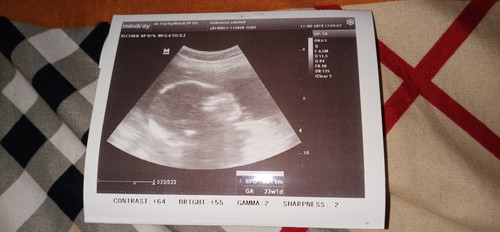

Setelah kuret sebanyak 2x penantian kehamilan akhirnya berakhir setelah menunggu selama 2 tahun. Selain rezki Hamil Allah SWT juga menghadiahkan kelulusan CPNS untuk saya sehingga perjalanan panjang kami dimulai Jambi(kerinci)- padang-medan-aceh (Lhoksmawe) kami lalui dengan tawa lepas dan bahagia. Alhamdulillah calon debaynya aktiv d usia 7bulan ini. #CeritaHamilTAP